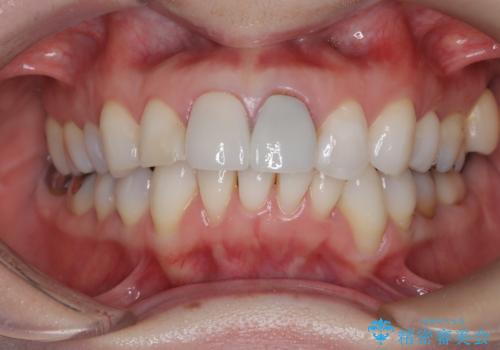

以前他院にてセラミッククラウンを被せていたのですが、セメントの劣化なのか色が青白くなっていました。

歯の形を整えた後、色が透けないよう処置をしてオールセラミッククラウンで治療を行いました。